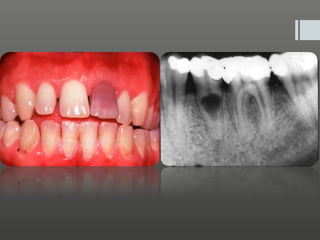

Clinical futures

Diagnosis

•P is already exposed and are may see layer of greyish ,

ulp

scum-like layer over the exposed pulp and surrounding

dentin .

•R

adiograph may show exposed pulp and caries under